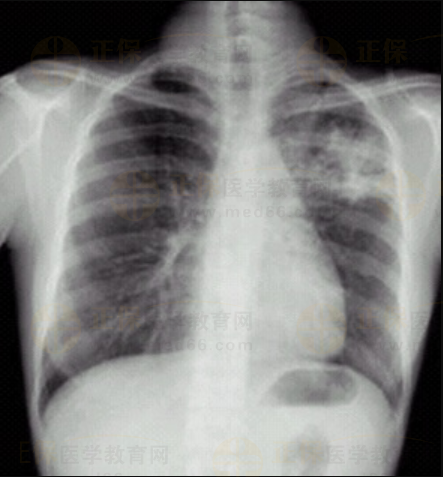

03卷-3.病史:男性,34歲,咳嗽、無痰半月,伴低熱。診斷。

A.左上支氣管擴(kuò)張

B.左上肺炎

C.左上浸潤型肺結(jié)核

D.左側(cè)胸腔積液

【該題針對“ X線-浸潤型肺結(jié)核 ”知識(shí)點(diǎn)進(jìn)行考核】